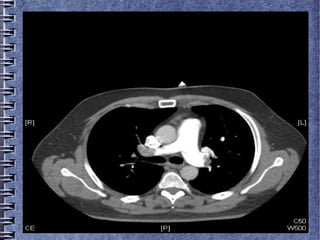

● AngioTAC: defectos de repleción (tromboémbolos flotantes)

en ambas arterias pulmonares principales que se extienden

hacia las arterias lobares y segmentarias.

● En ECG se objetiva FA a 144 lpm no conocida, de duración

inderminada, no refiere palpitaciones.

● Se realiza hemograma, bioquimica y hemostasia, destacando

un Dímero D de 3238. Marcadores de necrosis miocárdica en

rango de la normalidad. En la gasometría arterial basal: pH

7.40, pCO2 40, pO2 80, EB -1.3, SatO2 99%. La Rx de tórax

no muestra hallazgos significativos.

● En la venografía de MMII, se identifica un defecto de

repleción en el tercio medio de la vena femoral superficial

derecha, que se extiende hasta la vena poplítea.

● Realizada Ecocardiografía transtorácica donde no se objetiva

dilataciones de las cavidades cardíacas ni derrame

pericárdico.